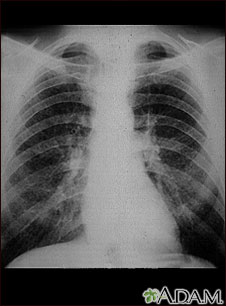

Pulmones de un trabajador del carbón; rayos X

Esta radiografía de tórax muestra los pulmones de un minero. A ambos lados de los pulmones hay áreas difusas, pequeñas (de 1 a 3 mm. cada una) y claras. Las enfermedades que pueden explicar estos hallazgos en una radiografía son la neumoconiosis del minero (NCM) etapa I, silicosis simple, tuberculosis miliar, histiocitosis X (granuloma eosinofílico) y otras enfermedades pulmonares infiltrativas difusas.